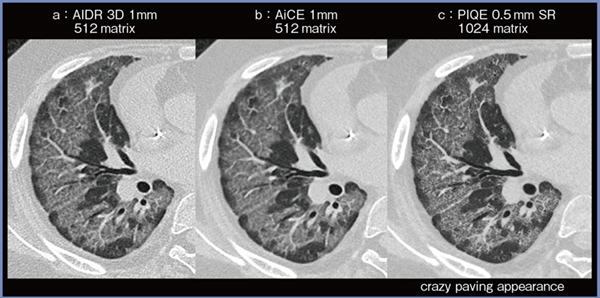

症例3は10歳代,男性,急性リンパ芽球性白血病治療後に肺胞蛋白症を合併した症例である。両肺にびまん性すりガラス影が見られ,その内部に網状影を認め,いわゆるcrazy-paving appearanceを呈していた(図4)。AiCE(図4 b)ではすりガラス内部の網状影が若干不明瞭であったが,PIQE(c)では非常に明瞭に描出されている。MPRでは,すりガラス影と正常肺が小葉単位で近接しており,すりガラス影が汎小葉性分布を呈していることが明確に把握できた。

図4 症例3:急性リンパ芽球性白血病治療後の肺胞蛋白症合併